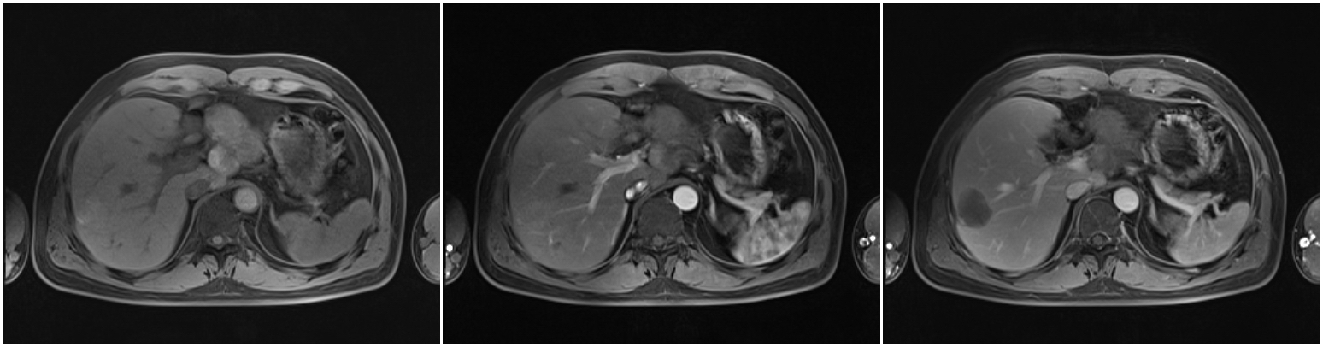

2012-02-22(第二次消融后2个月)复查PET/CT:肝脏病灶代谢未见异常。AFP:3.52 ng/ml。

2012-06-29(第二次消融)后6个月 复查PET/CT:肝脏病灶代谢未见异常。AFP:2.74 ng/ml。

患者术后每6个月复查MRI,无瘤生存一年半。

2013-07-17复查上腹部MRI:肿瘤边缘出现复发病灶。

2013-07-22 对复发病灶再次行微波消融治疗

术后患者规律于我院复查:末次上腹部MRI(2017-08-26)复查未见明显复发病灶;2017年08月26日AFP:1.71ng/ml。后患者定期于当地医院复查AFP,均正常范围。

电话随访至今,生存时间已达9年3个月。